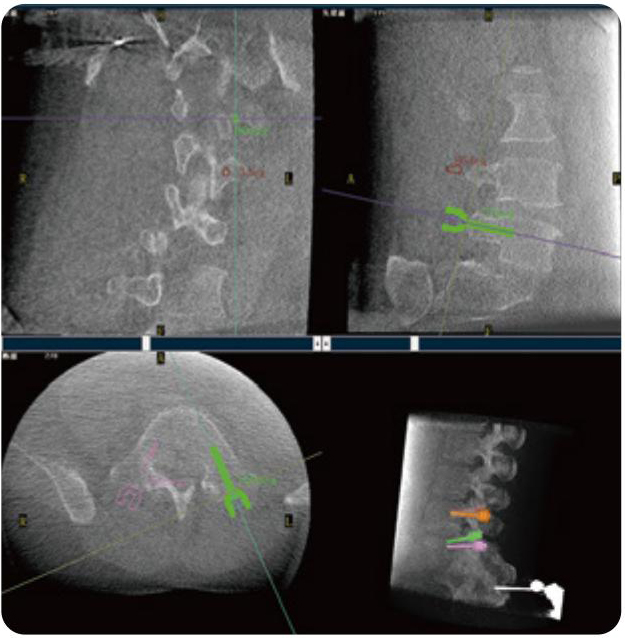

PL300B可應用于多節段脊柱外科手術,輔助醫生定位病灶部位,為脊柱外科手術(經皮椎體成形術、椎弓根螺釘內固定術等術式)提供術前手術流程規劃、入釘位置、角度可視化引導,模擬仿真入釘輔助。

PL300B搭配普愛醫療自主研發生產的平板3D C形臂,借助一體化自適應配準( 軌跡配準)技術,通過追蹤C形臂三維采集軌跡,自動完成圖像坐標建立和系統坐標配準。配準精度更高,操作步驟少,系統運作效率高。